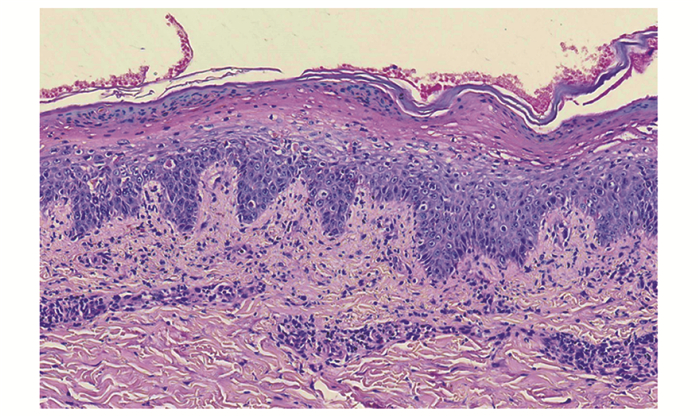

坏死松解性游走性红斑——胰腺占位一例

胡中慧, 杨璐, 刘跃华, 晋红中, 徐强, 刘雯静, 罗亚平, 阳洪波, 王涛

2023, 2(3): 427-431. DOI: 10.12376/j.issn.2097-0501.2023.03.014